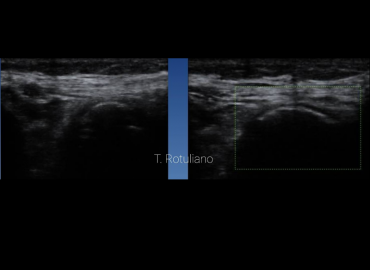

15 años. Gonalgia. Trauma hace 6 meses